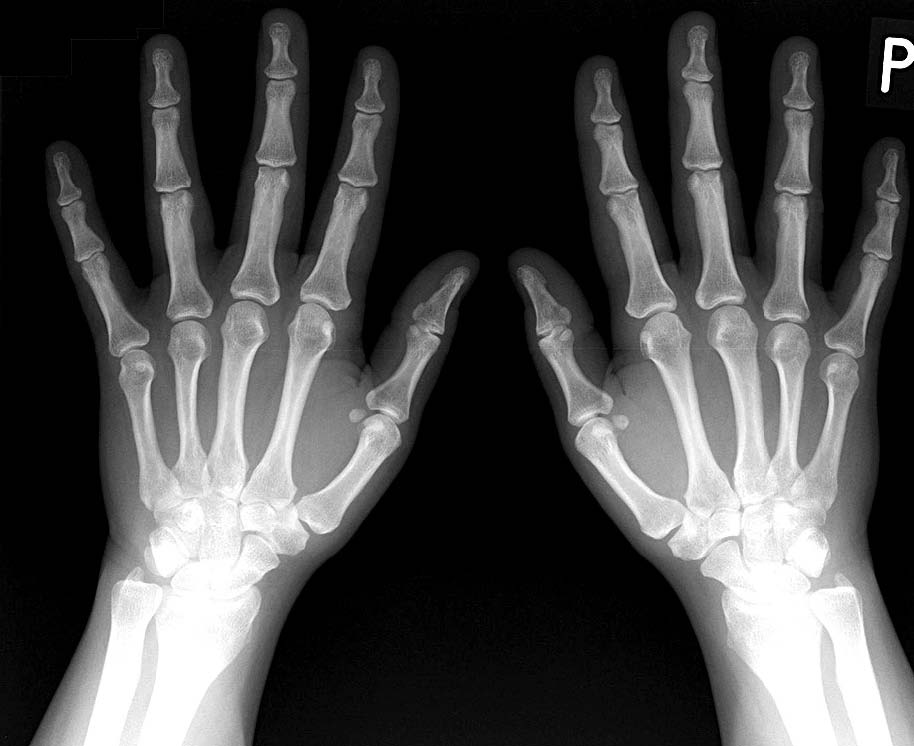

Choroba Stilla u dorosłych jest rzadko występującą chorobą układową tkanki łącznej, charakteryzującą się wysoką gorączką, zwiewną wysypką, zapaleniem stawów (ryc. 1 i 2), powiększeniem wątroby, śledziony, węzłów chłonnych oraz bólem gardła.